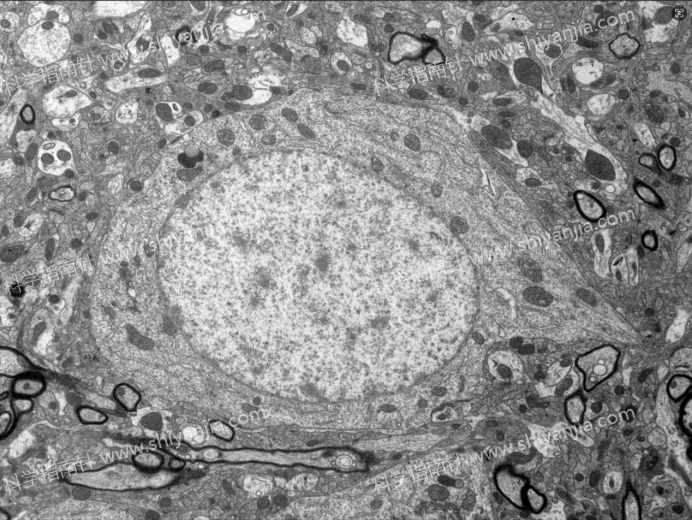

1.灌流处理是结构保存的基础:灌流组样本因固定液快速渗透组织,有效终止了酶促反应,样本结构保存效果远优于不灌流组;不灌流组即使 0 分钟快速取材,神经元也会出现早期自溶迹象。

灌流组

2.2 分钟是黄金取材窗口:灌流组 2 分钟内取材,样本超微结构无显著退化,膜结构清晰、细胞器形态完好,是兼顾操作可行性与样本质量的最佳时间。

灌流组